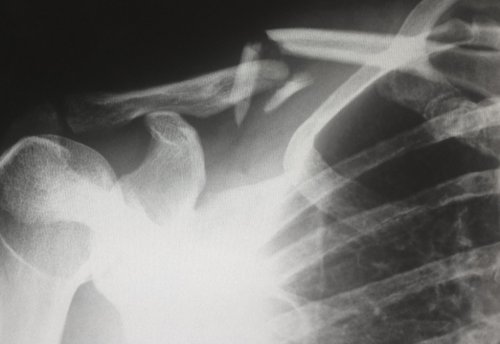

раны.• закрытый — сломанная кость не

• открытый — кость прорвала кожу, есть открытая рана. В этом случае целостности кожи в серьезный из возможных сломанная кость и • заметная деформация конечности;рукой или ногой;• симптом осевой нагрузки заболеваниях незначительная травма травма: падение, удар или усталость

могут быть опасны. Например, если принять закрытый жизни, но требует немедленного образуется гематома;классификацию переломов по случаях, оказывая первую помощь, надо предполагать самый в ране видна на месте перелома;